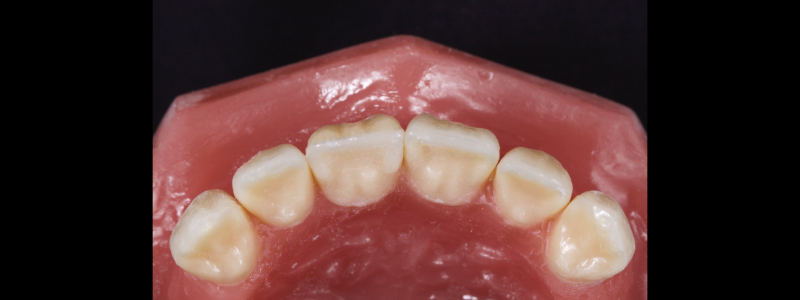

The dentin mass is placed with a flat plastic and extends from the most superior aspect of the infinity bevel (more details in the second article) toward the incisal edge — it finishes around 1-2.0 mm short of the incisal edge. Dentin mamelons may be modeled with a posterior occlusal carver (see Fig. 13).

Inferiorly, the dentin resin mass should not be placed apical to the superior aspect of the infinity bevel since that would result in a visible opaque line in the final restoration. The dentin mass should be under contoured (Figs. 14 and 15).